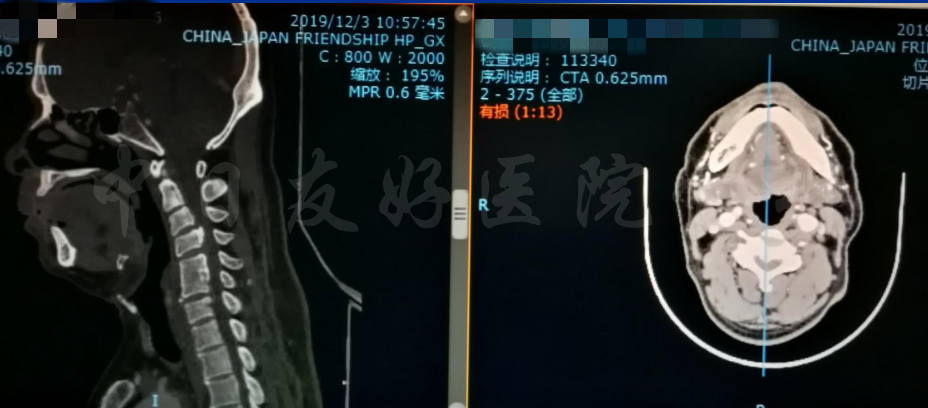

颈椎X片

颈CT(上下滑动)